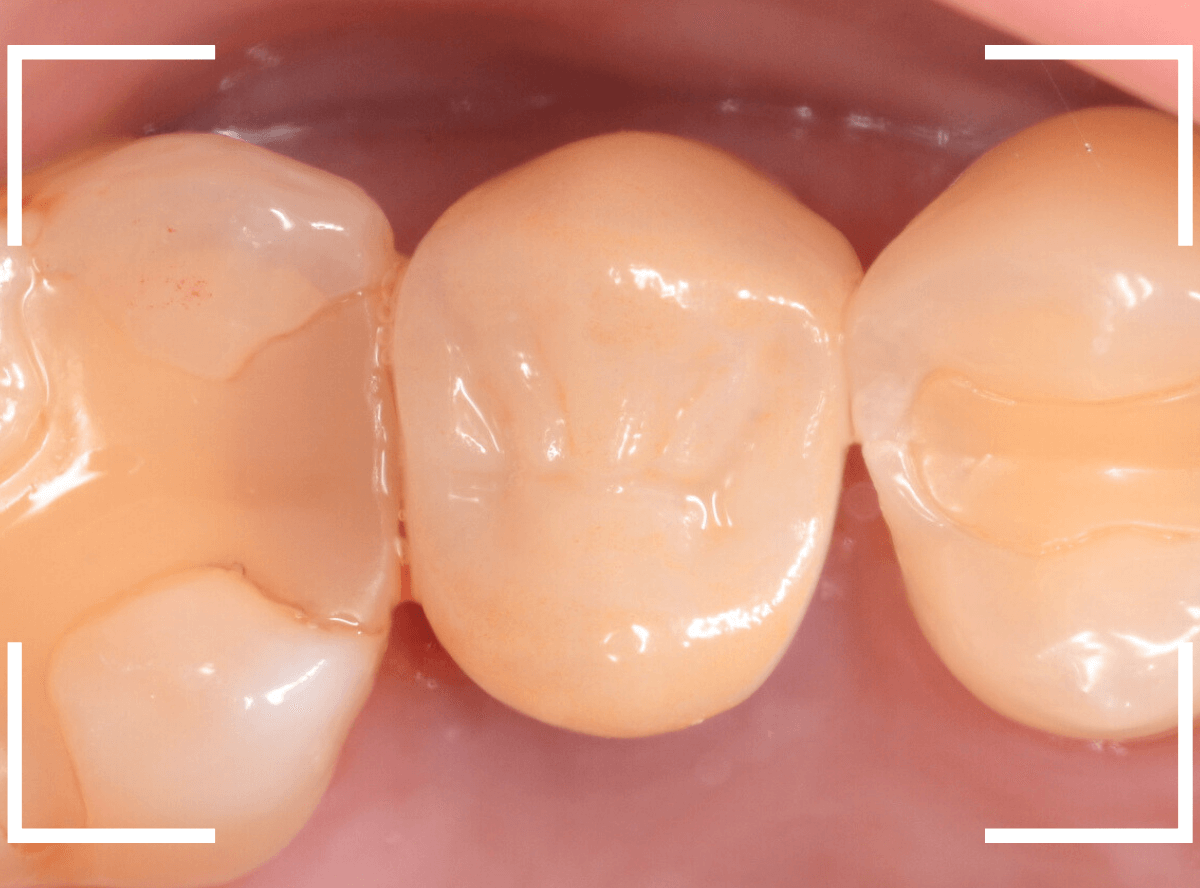

最終setした状態です。

患者さんにも満足いただける仕上がりなったかと思います。

治療前のCAD/CAM冠と、ジルコニア・クラウンの比較です。

CAD/CAM冠も見た目は白いですが、人工物っぽさが大きいのがわかると思います。

また、ジルコニアに比べると素材が脆弱で、長持ちさせるのは難しいです。